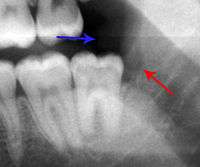

The periodontal ligament becomes inflamed and there may be pain when biting or tapping on the tooth. On an X-ray, bone resporption appears as a radiolucent area around the end of the root, although this does not manifest immediately.[9]:228 Acute apical periodontitis is characterized by well-localized, spontaneous, persistent, moderate to severe pain.[4]:125–135 The alveolar process may be tender to palpation over the roots. The tooth may be raised in the socket and feel more prominent than the adjacent teeth.[4]:125–135

- Radiographs utilized to find dental caries and bone loss laterally or at the apex.

Decay (green) with apical abscess (blue)